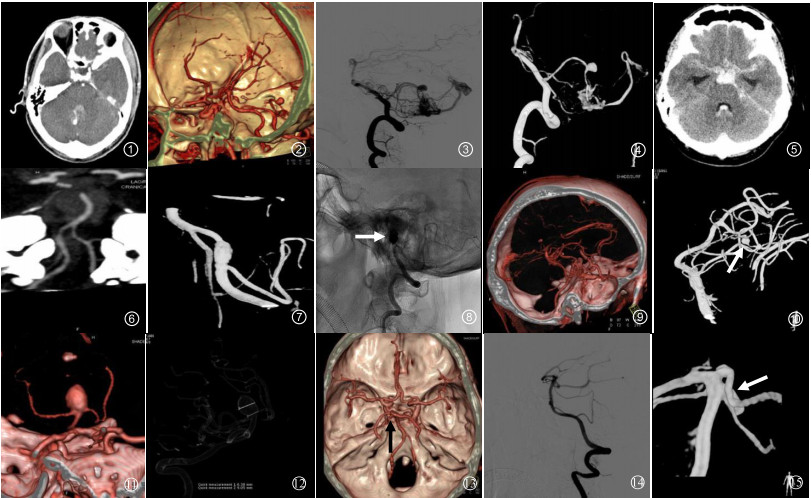

6例3D-CTA假阳性结果中,3例(50.0%)椎动脉V4段完全血栓机化CTA误诊为动脉瘤,1例(16.7%)小脑下动脉复合体误诊为小脑后下动脉瘤,2例(33.3%)小脑动静脉畸形合并小脑前下动脉动脉瘤漏诊为单纯囊状动脉瘤。5例(83.3%)动脉瘤直径≤5 mm,1例(16.7%)动脉瘤直径 > 5 mm,见图 1~4。

图 1 图 1~4 病例1:男,40岁,突发头痛伴呕吐1 d余。CTA原始轴位图像(图 1)示第四脑室后方囊袋状对比剂充盈影,周围见高密度出血,结合3D-CTA VR图像(图 2)考虑右侧小脑前下动脉出血性动脉瘤。2D-DSA及3D-DSA均可见动脉期有静脉早显现象,小脑前下动脉囊状动脉瘤的后方伴有畸形血管团和增粗的引流静脉,提示小脑动静脉畸形合并小脑前下动脉动脉瘤形成(图 3~4) 图 5~8 病例2:男,48岁,突发剧烈头痛、呕吐1 d。查头颅CT提示SAH、脑室积血(图 5)。MIP图像见左侧椎动脉颅内段局部血管痉挛改变,未见明确动脉瘤(图 6)。DSA显示左侧椎动脉V4段(小脑后下动脉分叉处以远)串珠征及双腔征改变,提示夹层动脉瘤(图 7 3D-DSA;图 8急诊栓塞后DSA,白箭头示弹簧圈) 图 9~10 病例3:女,43岁,突发头疼2 d。自发性SAH患者,3D-CTA检查均未见动脉瘤(图 9)。3D-DSA清晰可见左侧小脑上动脉远段分支小囊状染色,诊断为左侧小脑上动脉远段小动脉瘤破裂(图 10, 白箭头示) 图 11~12 病例4:男,58岁,突发头痛伴恶心、呕吐1 d。3D-CTA和3D-DSA均可清楚地显示基底动脉尖直径9 mm动脉瘤,并具有更直观的3D效果,真实显示了瘤体形态、瘤颈及动脉瘤与载瘤动脉的空间关系(图 11 CTA VR图像;图 12 DSA三维透明法) 图 13~15 病例5:女,54岁,突发意识障碍伴头痛、呕吐2 d。3D-CTA考虑左侧大脑后动脉起始部动脉瘤(图 13, 黑箭头示)。12 h后行常规DSA及3D-DSA检查(图 14~15)。因注入的对比剂量增加,对细节的显示更清楚,DSA准确显示动脉瘤位于左侧小脑上动脉近段(图 15, 白箭头示) |

42例3D-CTA假阴性结果中,12例(28.6%)椎动脉V4段,18例(42.9%)小脑后下动脉,6例(14.3%)小脑前下动脉,3例(7.1%)小脑上动脉以及2例(4.8%)基底动脉动脉瘤未诊断,1例(2.4%)小脑上动脉动脉瘤表现为同侧大脑后动脉动脉瘤。37例(88.1%)动脉瘤直径≤5 mm,其中24例(57.1%)动脉瘤直径≤3 mm,13例(31.0%)动脉瘤直径 > 3 mm且≤5 mm,另外5例(11.9%)动脉瘤直径 > 5 mm,图 5~10。

本研究发现3D-CTA显示颅内后循环各部位的出血性动脉瘤均有很高的特异度,对基底动脉动脉瘤、大脑后动脉动脉瘤诊断的敏感度和准确率较高(图 11~12病例4),但是,显示椎动脉V4段动脉瘤、小脑后下动脉动脉瘤、小脑前下动脉动脉瘤及小脑上动脉动脉瘤的敏感度均低于85%。笔者认为这可能是由于椎动脉V4段动脉瘤、小脑后下动脉动脉瘤、小脑前下动脉动脉瘤及小脑上动脉动脉瘤靠近颅底,CTA图像易受颅底骨质伪影干扰;部分载瘤动脉血管较细,血流相对较少,特别是二级以下分支血管,注入的对比剂经血流稀释后显影不清;也可能是由于动脉瘤破裂出血后,周围的氧合血红蛋白对血管壁的刺激,加之红细胞在其降解过程中一些分解产物和神经递质释放的影响,引起载瘤动脉血管痉挛改变,使CTA检出困难。

与3D-DSA结果进行对照研究,发现存在一些假阳性和假阴性的结果值得进一步讨论。本研究中,3例CTA显示假阳性直径均 < 5 mm的椎动脉V4段动脉瘤最后被证实为完全血栓闭塞性动脉瘤,1例小脑下动脉复合体由于走行迂曲、成襻,CTA显示为小脑后下动脉动脉瘤样表现,2例小脑动静脉畸形合并小脑前下动脉动脉瘤漏诊为单纯小脑前下动脉囊状动脉瘤。因此,对于颅内后循环动脉尤其是椎动脉内CT平扫呈高密度且CTA显示瘤样膨隆的病变,应考虑到动脉瘤完全血栓机化的可能。而对于后循环血管变异或合并有其他血管畸形时,应注意在CTA后处理过程中多方位、多角度观察,仔细辨别是否存在假象,避免造成误诊的可能。

本研究中1例小脑上动脉近段动脉瘤误诊为同侧大脑后动脉动脉瘤(图 13~15病例5),与3D-DSA对照分析,发现此例患者3D-CTA图像上左侧大脑后动脉未显影。笔者认为这可能与CTA检查时靶血管的对比剂浓度较低或血流动力学影响有关。由于DSA超选至双侧椎动脉对颅内后循环动脉进行检查,而CTA是从外周静脉注入对比剂经肺循环后对靶血管薄层扫描。因此,与DSA相比,CTA流入靶血管的对比剂浓度低,对血流动力学影响轻微,故对侧支循环情况显示不如DSA。